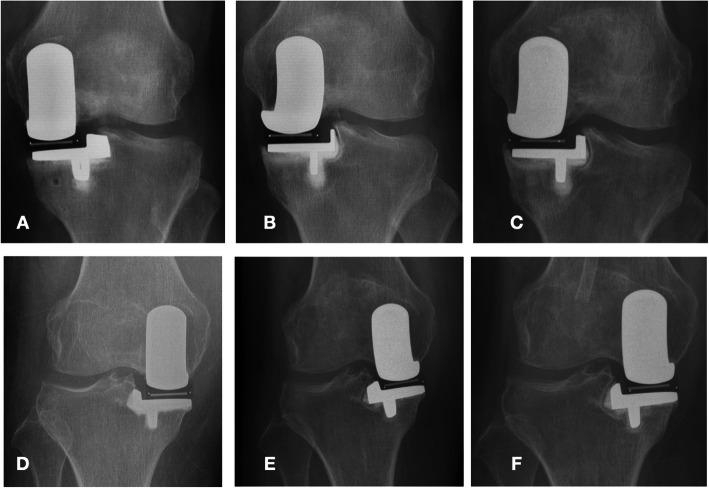

The use of Oxford Unicompartmental Knee Arthroplasty (UKA) has increased rapidly in both Western and Asian populations, with excellent functional outcomes and high patient satisfaction. While previous evidence regarding clinical outcomes and survival rates after Oxford UKA was based on studies in Western populations, the results may be different in Asian patients. The relevance of age for postoperative function after Oxford UKA also remains unclear. Hence, the aim of our study was to clarify the effectiveness and safety of Oxford UKA in Asian patients aged over 80 years.

METHODS

A retrospective review was performed and included 195 patients (209 knees) who underwent an Oxford UKA between June 2015 and July 2018. We divided the patients into three groups by age: Group 1, 60-69 years; Group 2, 70-79 years; and Group 3, over 80 years. We used the Hospital for Special Surgery (HSS) score and Western Ontario and McMaster (WOMAC) Universities Osteoarthritis Index score to evaluate the general condition of the patients' knees before surgery and at last follow-up. We also recorded perioperative and short-term complications.

Group 1 consisted of 60 patients (60 knees); Group 2, 70 patients (79 knees); and Group 3, 65 patients (70 knees). The mean follow-up was 21.34 ± 12.04, 22.08 ± 11.38, and 21.76 ± 10.20 months in groups 1, 2, and 3, respectively. At last follow-up, the patients in Group 3 showed lower function scores compared to groups 1 and 2 (P < 0.05), but the HSS scores and the WOMAC scores were significantly improved in all three groups. In terms of perioperative and other complications, the three age groups did not differ significantly.